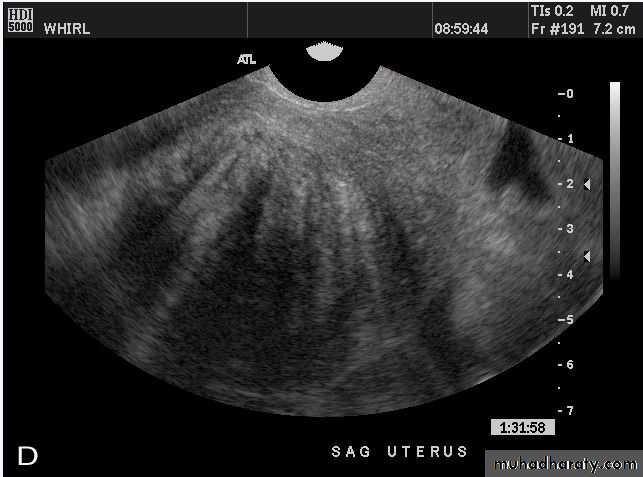

Normal Uterus in longitudinal viewUterine Pathology